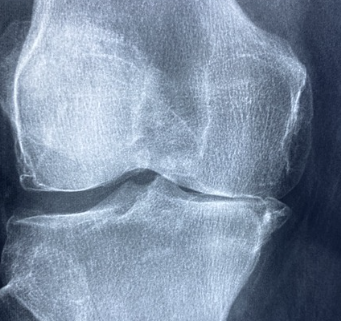

류마티스 관절염은 뼈와 관절, 근육, 힘줄 등을 연결하는 연조직의 염증으로 인해 발생하는 질환입니다. 나이가 들수록 발생 확률이 높아지며, 여성이 남성보다 발생률이 높은 편입니다. 이번 글에서는 류마티스 관절염의 증상에 대해 알아보도록 하겠습니다.

류마티스 관절염은 면역 체계의 오작동으로 인해 발생하는 만성 관절염으로, 주로 손, 발, 무릎, 손목 등의 작은 관절에 영향을 미칩니다.

류마티스 관절염은 조기 발견과 적절한 치료가 중요합니다. 류마티스 관절염 초기 증상이 의심되면 전문가와 상담하고 적절한 치료를 받는 것이 중요합니다. 조기 치료를 통해 증상을 완화하고 관절 손상을 예방할 수 있습니다.